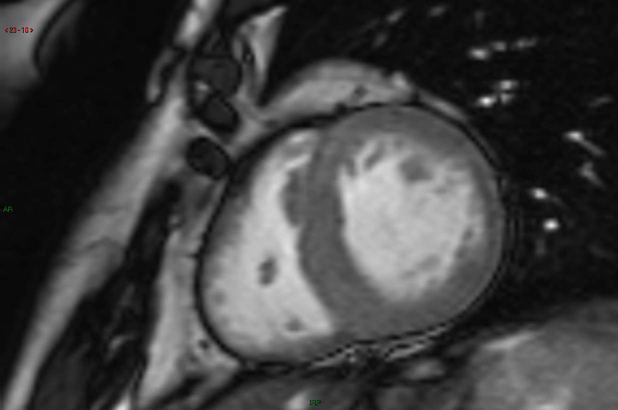

Définition : zone ou portion de la paroi ventriculaire caractérisée par une diminution d'épaississement au cours de la systole.  <

Reconnaître : par définition, une zone hypokinétique ne peut être visualisée que sur des coupes dynamiques en mode ciné-IRM. Il convient de repérer la zone caractérisée par une diminution de contraction lors de la systole en la comparant à d'autres portions pariétales de contraction normale. La difficulté est de correctement distinguer une diminution de contraction des mouvements passifs qui continuent d'animer de proche en proche l'ensemble de la paroi ventriculaire. En fonction des habitudes, les coupes réalisées avec un marquage tissulaire à l'aide de bandes de présaturation (tagging) peuvent aider à repérer une zone hypokinétique. Il faut préciser la localisation de la zone hypokinétique et notamment chercher une distribution vasculaire (paroi antérieure : interventriculaire antérieure ; paroi latérale : circonflexe ; septum inférieur : coronaire droite).  <

Éléments associés : il faut chercher d'autres zones akinétiques ou dyskinétiques, un rehaussement tardif sur les coupes réalisées à distance de l'injection de produit de contraste. Il faut chercher de façon systématique un thrombus en regard de la zone hypokinétique.  <

Étiologie : au niveau ventriculaire gauche, les zones hypokinétiques sont le plus fréquemment la conséquence d'une cardiopathie ischémique. Au niveau ventriculaire droit, les zones hypokinétiques sont le plus fréquemment observées au cours d'une dysplasie arythmogène du ventricule droit.  <